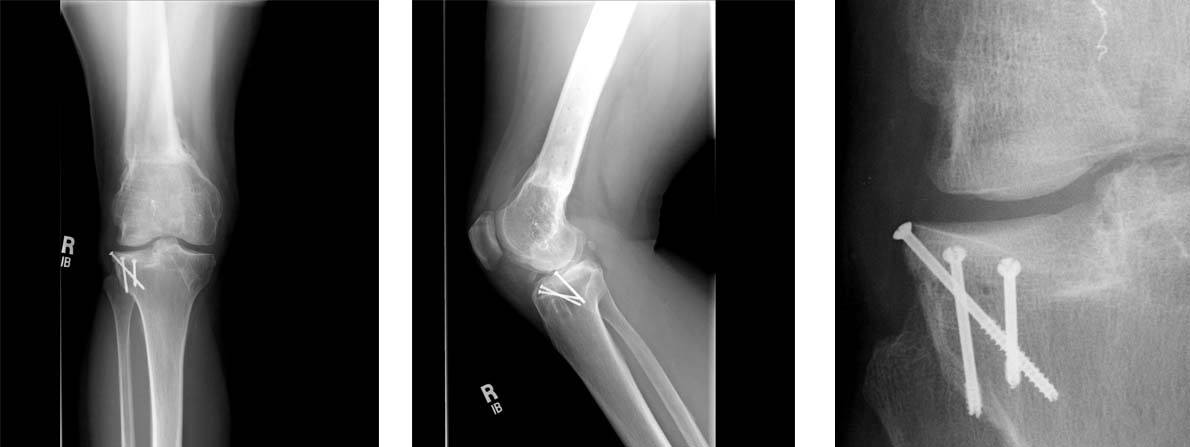

7.The final radiographs show the multiple screws used to fix the tibial graft. No fixation was required for the graft on the femur. On the closeup image on the right, one can see the interface between the tibia and the graft (large arrows) as well as the bony surface of the graft on the femur (small arrows). The patient's symptoms of knee pain have nearly fully resolved with the surgery.